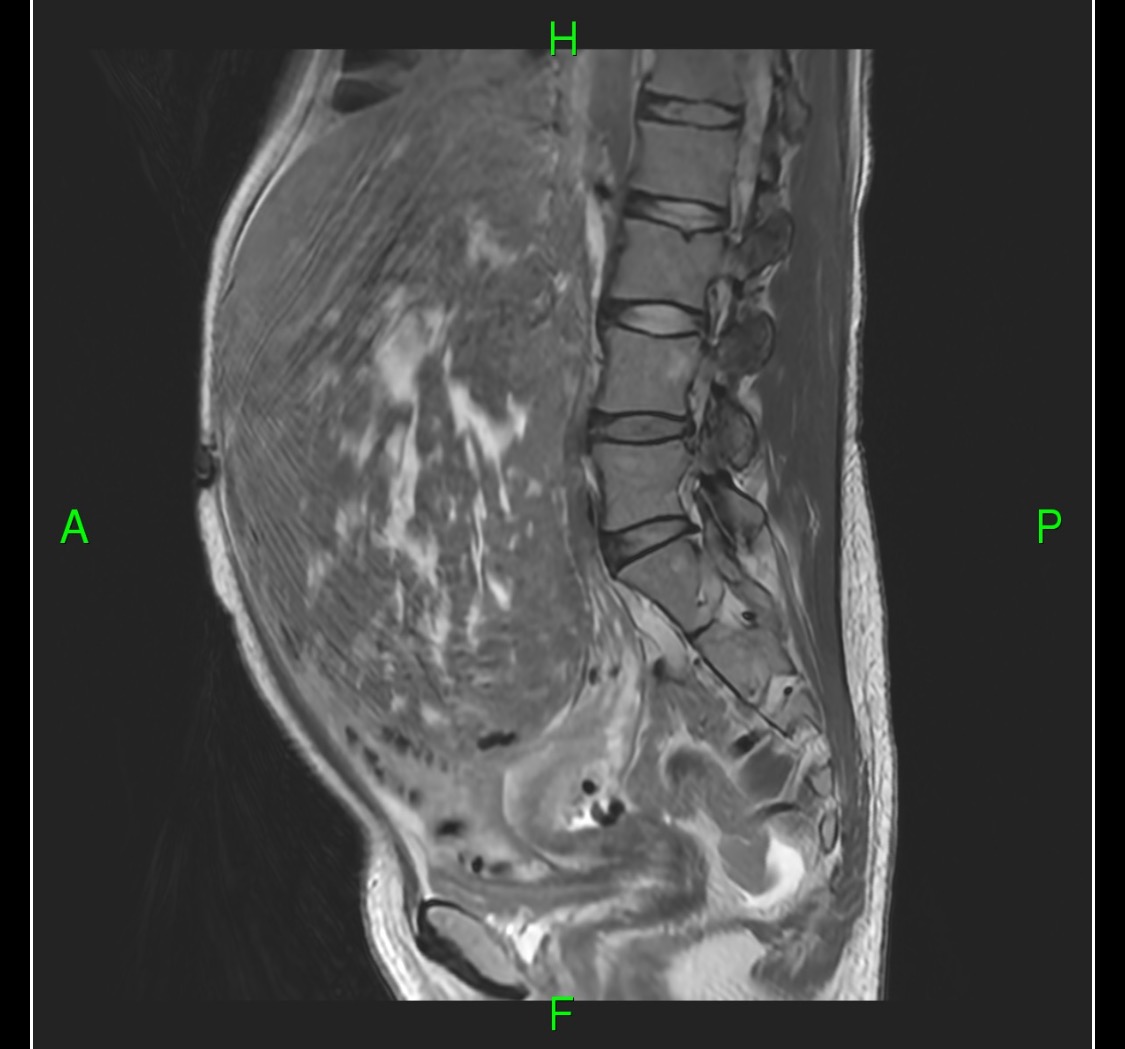

Amy recently discovered she has a watermelon-sized mass growing inside her. It’s going to be a big surgery, and she’s going to be out of work for at LEAST two months.